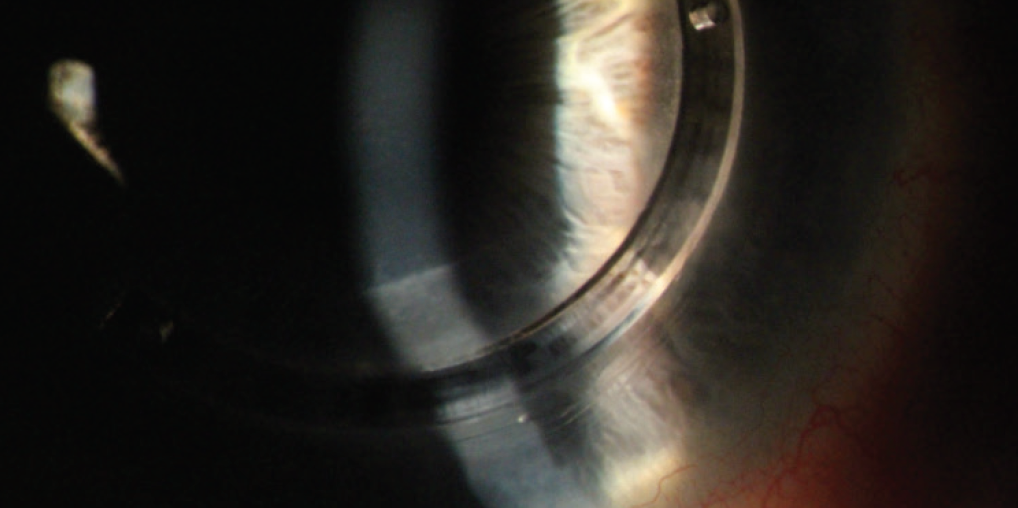

Cons

In many cases, an ICRS can reduce corneal protrusion, but the magnitude of the flattening effect is often unpredictable. Moreover, implanting synthetic material into deep stroma carries risks, the biggest of which is stromal melting (Figure 1).5 The most common cause of ICRS-induced corneal melts is ring migration toward the incision site, but thin corneas preoperatively, eye rubbing, ectatic progression, corneal trauma, and corneal infiltrates or ulcers are all predisposing factors.5 Figure 1. Valley in the slit-lamp beam signifying inferior ICRS melt nearly 1 year after implantation. The risk of corneal melts warrants consideration, particularly for young patients. ICRSs are likely best suited to patients for whom contact lenses have failed and who are looking for a treatment method to defer the need for a corneal transplant. In addition, Kanellopoulos and colleagues are studying a combination of porcine xenograft ICRSs with CXL, which has shown promise of corneal flattening in early results.6 If proven viable, this new ICRS implantation strategy may reduce the risks of complications such as stromal melt and corneal erosion. No. 4: Topography-Guided PRK Topography-guided PRK (TG-PRK) incorporates unique shape data from each patient’s cornea into a laser ablation profile. The primary goal of treatment is to regularize the anterior corneal shape with the minimal amount of tissue ablation. Although not FDA approved for use in irregular corneas, some surgeons are offering this technology as an off-label treatment for irregular corneas. With TG-PRK, surgeons can focus treatment on particular areas of the cornea, titrating the resultant corneal flattening. Particularly for keratoconus patients after CXL, this means focalized flattening at the cone apex while minimizing ablation centrally and superiorly (Figure 2). Figure 2. This patient’s visual acuity was 20/70 before he underwent TG-PRK in the left eye. Preoperative anterior segment tomography (Pentacam, Oculus) results are shown at left. At 1 month postoperative the eye was very dry with superficial punctate keratitis, but UCVA was 20/60. Tomography images at 6 months post–TG-PRK are shown at right. There is evidence of 4.00 D of inferior flattening, whereas superiorly there is steepening resulting from peripheral laser treatment. Pros TG-PRK can be combined with CXL during the same treatment session or at separate times in a staged treatment process. With TG-PRK, eye care providers can offer refractive surgery to patients who have keratoconus in order to regularize their corneal profile and thereby improve BCVA and perhaps UCVA. This is generally an exciting prospect for patients. Discussion of TG-PRK can also augment efforts to educate patients about the goal of CXL (ie, to maintain rather than drastically improve BCVA). Cons Protocols and large volumes of patients have not been well studied in the United States. Patient education is essential because the results of TG-PRK are variable after CXL. The key to maximum success with refractive and optical technologies in patients with keratoconus is first to stabilize their ectasia with CXL. The new paradigm for this patient population should be early diagnosis followed by early CXL and finally refractive or optical rehabilitation. A recent study provided evidence in support of this approach. In a retrospective analysis of the effectiveness of CXL for treating keratoconic eyes, those with a baseline Kmax value that was greater than or equal to 58.00 D had a much higher risk of keratoconic progression than has been previously reported.7 Although advanced disease severity does not necessarily exclude CXL as a valid intervention,8 this study does highlight the abundance in clinical benefits when patients are provided early access to CXL. 1. Ferdi AC, Nguyen V, Gore DM, Allen BD, Rozema JJ, Watson SL. Keratoconus natural progression: a systematic review and meta-analysis of 11 529 eyes. Ophthalmology. 2019;126(7):935-945. 2. Kennedy RH, Bourne WM, Dyer JA. A 48-year clinical and epidemiologic study of keratoconus. Am J Ophthalmol. 1986;101(3):267-273. 3. Belin MW, Lim L, Rajpal RK, Hafezi F, Gomes JAP, Cochener B. Corneal cross-linking: current USA status: report from the Cornea Society. Cornea. 2018;37(10):1218-1225. 4. Hersh PS, Stulting RD, Muller D, Durrie DS, Rajpal RK; United States Crosslinking Study Group. United States multicenter clinical trial of corneal collagen crosslinking for keratoconus treatment. Ophthalmology. 2017;124(9):1259-1270. 5. Jarade E, Issa M, Chanbour W, Warhekar P. Biologic stromal ring to manage stromal melting after intrastromal corneal ring segment implantation. J Cataract Refract Surg. 2019;45(9):1222-1225. 6. Kanellopoulos AJ, Vingopoulos F. Combining porcine xenograft intra-corneal ring segments and CXL: a novel technique. Clin Ophthalmol. 2019;13:2521-2525. 7. Kuechler SJ, Tappeiner C, Epstein D, Frueh BE. Keratoconus progression after corneal cross-linking in eyes with preoperative maximum keratometry values of 58 diopters and steeper. Cornea. 2018;37(11):1444-1448. 8. Ivarsen A, Hjortdal J. Collagen cross-linking for advanced progressive keratoconus. Cornea. 2013;32(7):903-906.